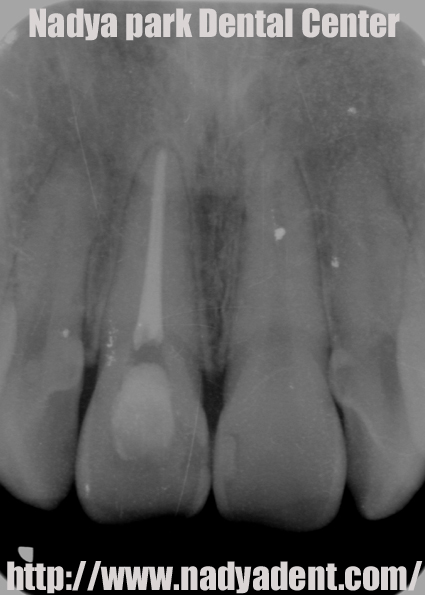

審美歯科 予防歯科 小児歯科 名古屋 症例

上の写真は根の治療の後のレントゲン写真です。

根の治療を終え、歯の神経が入っていたスペースに漂白の薬剤を置きます。